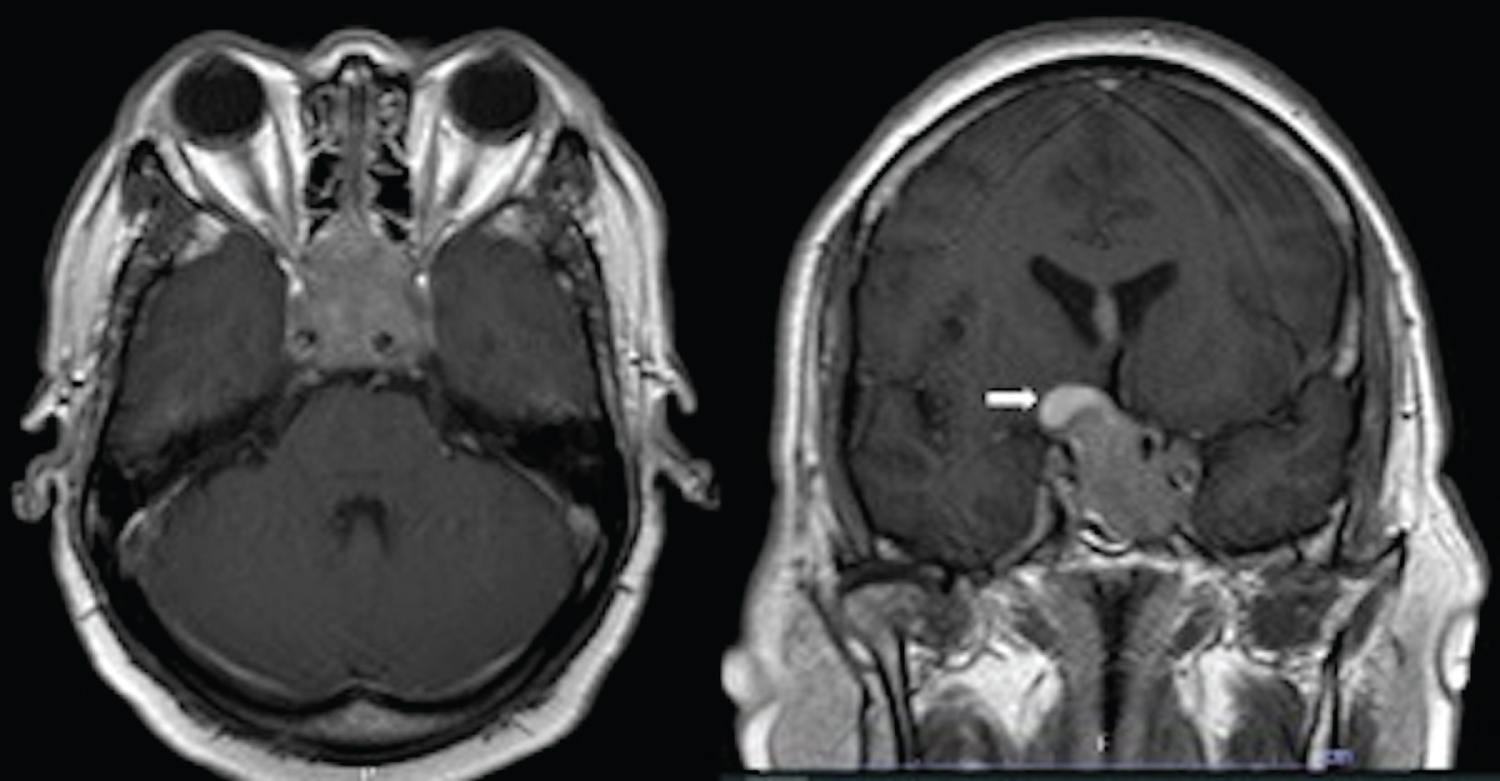

A 57-year-old man presented with sudden blurred vision and right-sided weakness. He had progressive headache five days prior to admission. The patient also had a history of hypertension and right-foot leprosy, which was amputated 10 years ago. On physical examination, the patient was fully conscious. He had visual acuity of 20/200 in both eyes. Visual field test revealed bitemporal hemianopia. Right-sided motor power was rated at grade 2. He had no cutaneous stigmata, history of tumors in other organs, or familial tumors. Magnetic resonance imaging (MRI) of the brain showed two discrete heterogeneous enhancing tumors at the sellar region and in bilateral lateral ventricles. Both tumors were isointense on T1-weighted and heterogeneously hyperintense on T2-weighted images. The sellar tumor was measured 4.0 × 3.4 × 3.2 cm in diameter with hemorrhagic content at the right superior aspect of the tumor. It extended into bilateral cavernous sinuses, sphenoid sinus, and suprasellar area which compressed optic chiasm and the third ventricle (Figure 1). The intraventricular tumor, measured 4.0 × 4.3 × 5.4 cm in diameter, was located in the body of lateral ventricles. It involved the body of corpus callosum, mainly in the left side, with adjacent periventricular brain edema (Figure 2). Blood levels of pituitary hormones were within normal range, and serum tumor markers, including alpha fetoprotein, beta human chorionic gonadotropin, carcinoembryonic antigen, and prostate-specific antigen, were unremarkable. There was no evidence of seeding metastasis on MRI of the whole spine.

Figure 1: Contrast-enhanced T1-weighted MRI of the brain showing sellar tumor involving bilateral cavernous sinuses, pituitary gland, infundibulum, and optic chiasm in axial (left) and coronal views (right) with hemorrhage at the right superior aspect (white arrow). View Figure 1